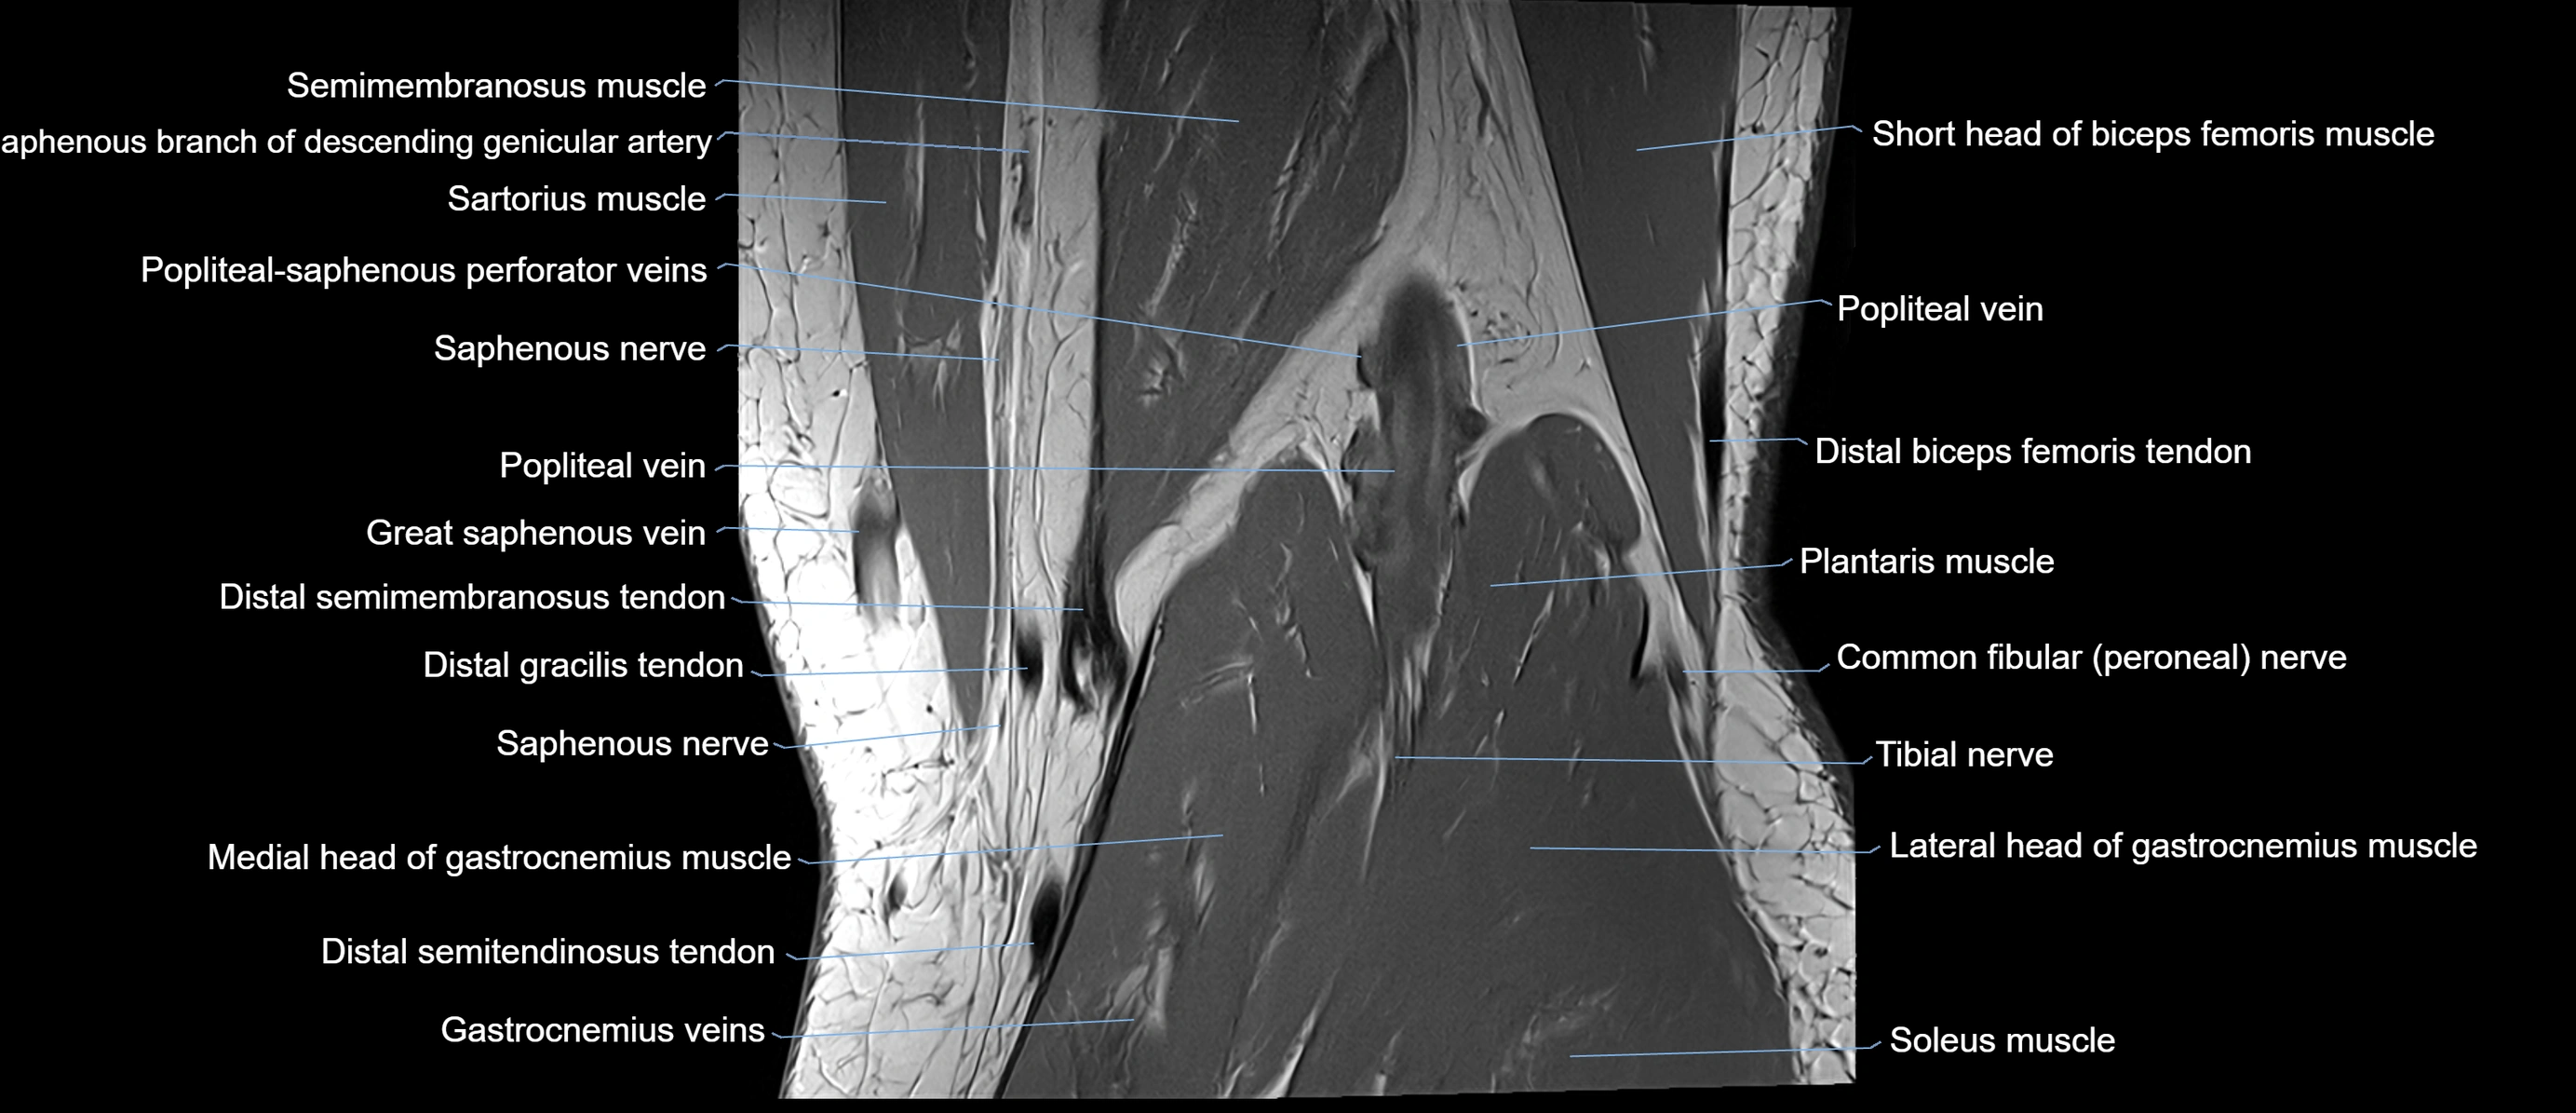

- Semimembranosus muscle

- Sartorius muscle

- Popliteal–Saphenous perforating veins

- Saphenous nerve

- Popliteal vein

- great saphenous vein

- Distal semimembranosus tendon

- Gracilis tendon (Distal)

- Medial head of gastrocnemius muscle

- Distal semitendinosus tendon

- Biceps femoris muscle (Short head)

- Distal biceps femoris tendon

- Plantaris muscle

- Common fibular nerve

- Tibial nerve

- Lateral head of gastrocnemius muscle

- Soleus muscle

- Lateral sural cutaneous nerve

- Medial sural cutaneous nerve